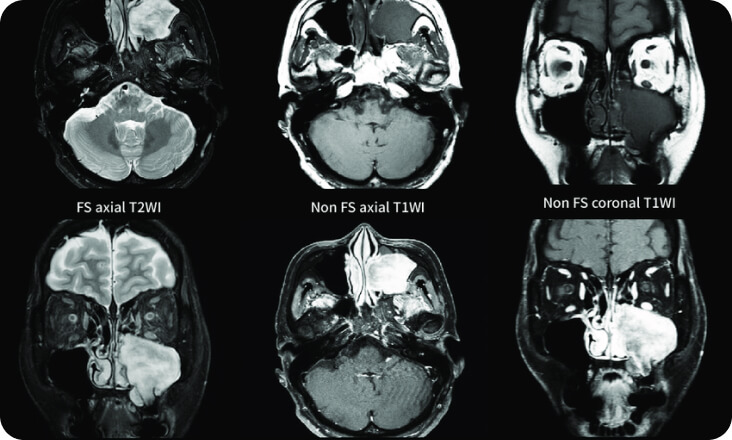

MRI Đầu cổ

Chụp sọ não, vùng cổ, mạch máu, cột sổng cổ, khớp thái dương hàm, tai họng

Chất lượng hình ảnh tốt, ít nhiễu ảnh.

Ứng dụng MRI sọ não nâng cao:

- MRI tươi máu

- MRI Chức năng

- MRI tai trong

- MRI phổ – MRI khuếch tán sợi trục thần kinh